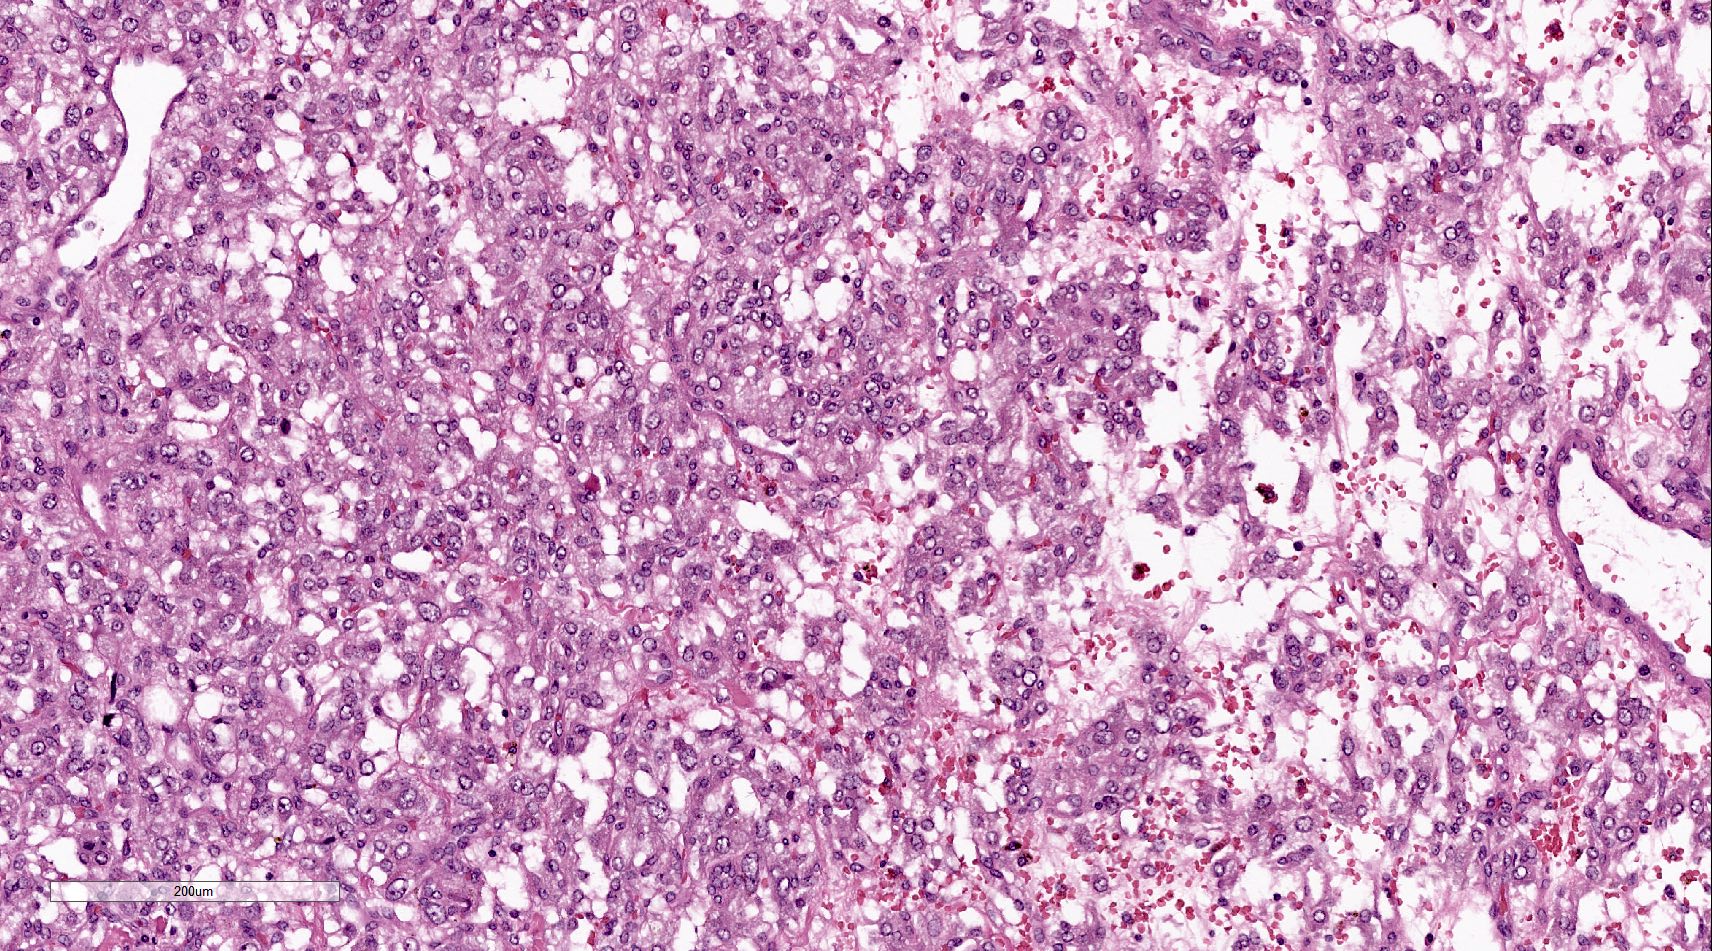

Microscopic (histologic) description

- Prevailing histologic pattern: epithelioid chief cells arranged in distinctive clusters / nests (zellballen pattern), separated by prominent fibrovascular stroma (J Clin Med 2018;7:280)

- Trabecular pattern: ribbons or cords of epithelioid cells divided by fibrous bands

- Other patterns: pseudorosette, angioma-like, spindled and sclerosing

- Chief cells: round, oval to polygonal cells with abundant granular basophilic, eosinophilic or amphophilic cytoplasm (Surg Pathol Clin 2019;12:951)

- Intracytoplasmic hyaline globules may be present in sympathoadrenal paragangliomas

- Giant multinucleated cells and bizarre cells can be present (Srp Arh Celok Lek 2002;130:7)

- Rarely, elongated and spindle shaped cells with a sarcomatoid appearance may be found

- Scattered ganglion cells can be seen

- May have nuclear atypia

- May have dysmorphic vessels, melanin-like pigment (neuromelanin) (pigmented paraganglioma), amyloid, abundant stroma and osseous metaplasia (Diagn Pathol 2012;7:77, Hum Pathol 1992;23:33)

- No or rare mitotic figures except in highly aggressive rapidly proliferating lesions

- May have focal chronic inflammatory infiltrate

- Necrosis is unusual except in patients who have undergone preoperative tumor embolization

Microscopic (histologic) images

Contributed by Luvy Delfin, M.D. and Sylvia L. Asa, M.D., Ph.D.